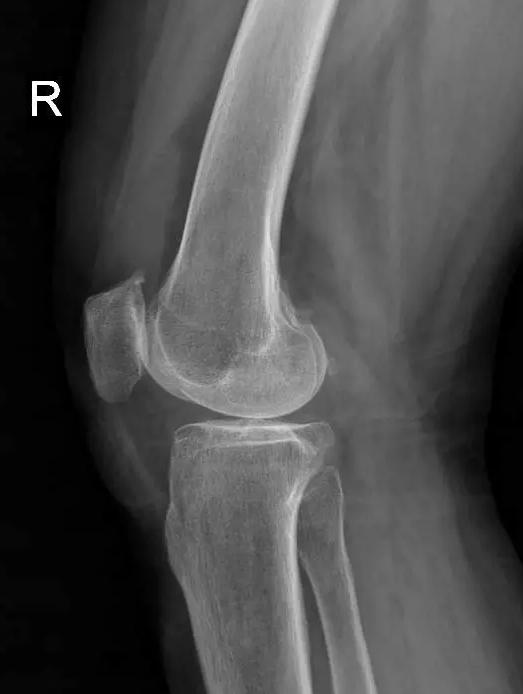

术前片:

术后图如下: